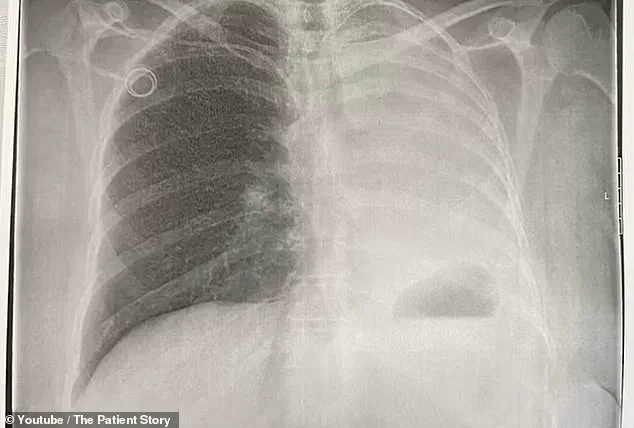

Though she emerged unscathed, the hospital’s routine X-ray revealed an unusual mass in her abdominal area.

Initially, doctors believed it was in an early stage, but as the months passed, the cancer spread to her bones and one of her lungs, eventually leading to a stage four diagnosis in 2022.

By the time her cancer was discovered to have metastasized from her uterus to her lung, the physical toll was already evident.